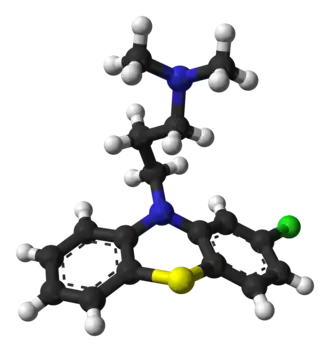

Все антипсихотики блокируют рецепторы дофамина типа D2, степень блокировки ими других значимых нейромедиаторных рецепторов варьирует[153]. Многие из типичных нейролептиков подавляют только рецепторы D2, а большинство атипичных воздействуют одновременно на целый ряд нейромедиаторных рецепторов: дофамина, серотонина, гистамина и других[153].

Имеются свидетельства того, что клозапин, амисульприд, оланзапин и рисперидон являются самыми эффективными из антипсихотиков[201]. Дальнейшее (после купирования психоза) их применение позволяет снизить риск рецидива[202][203].

При применении антипсихотиков хороший ответ наблюдается у 40—50 % пациентов, частичный у 30—40 %, а у 20 % обнаруживается резистентность к лечению (отсутствие удовлетворительной реакции на два или три лекарства после шести недель их приёма)[181]. В тяжёлых случаях и среди тех, кому не помогают другие антипсихотики (при так называемой «резистентной шизофрении»[204][205]), рекомендуется назначение клозапина[206][207] — препарата, отличающегося повышенной эффективностью, но несущего риск потенциально смертельных побочных эффектов, в том числе агранулоцитоза и миокардита у 4 % больных[208][209]. Клозапин является единственно доказанным медикаментом при резистентной шизофрении (до 50 % эффективности)[210]. Он может обладать и дополнительным преимуществом, предположительно снижая склонность к алкоголизму, наркомании и самоубийству у больных шизофренией[211]. Подавляя развитие костного мозга, клозапин снижает уровень лейкоцитов, что может привести к инфекции, поэтому при использовании этого препарата в первые шесть месяцев регулярно проводят анализ крови[212].

Несмотря на более высокую стоимость, атипичные антипсихотики всё же предпочтительнее при начальном выборе терапии перед более старыми, «типичными»: они, как правило, легче переносятся, и их использование реже сопровождается поздней дискинезией. Впрочем, некоторые из атипичных антипсихотиков чаще, чем типичные, вызывают набор веса и заболевания, связанные с ожирением, — особенно это касается рисперидона, кветиапина, оланзапина, применение которого связано с высоким риском сахарного диабета и метаболического синдрома[201][213], и клозапина, который тоже часто может вызывать метаболические нарушения и сахарный диабет[214]. Также у людей, получающих некоторые из атипичных антипсихотиков, отмечаются случаи повышения уровня пролактина, галактореи и опухоли гипофиза[215][216] — как и при приёме типичных антипсихотиков. Остаётся неясным, снижает ли переход на более новые лекарства шансы развития злокачественного нейролептического синдрома — редкого, но тяжёлого и потенциально смертельного неврологического расстройства, чаще всего возникающего как отрицательная реакция на антипсихотики[217].